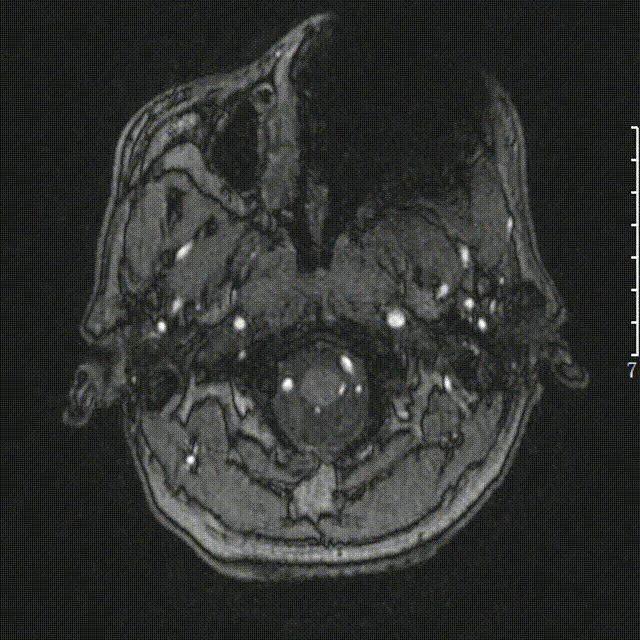

头颅MRA:右侧颈内动脉闭塞。